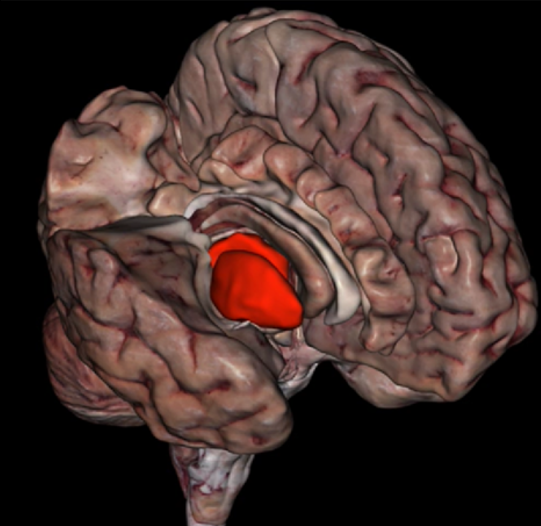

Caudate Nucleus

Putamen

Thalamus

Thalamus